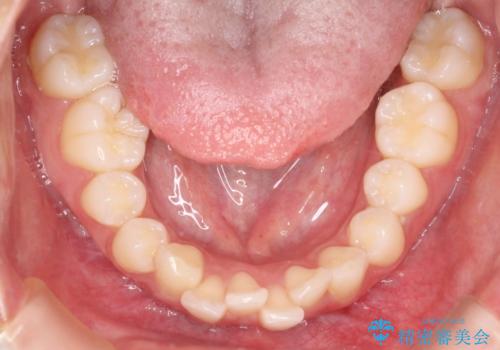

1. 【審美ワイヤー】口元を下げたいの治療前